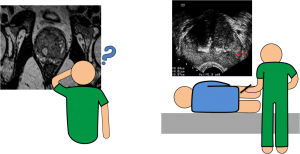

Biópsia prostática orientada por fusão de imagem (RM-US)

A técnica de biópsia mais frequentemente realizada e aceita como atual método de referência é a biópsia prostática randômica em duplo sextante guiada por ultrassonografia transretal.

Por outro lado a  ressonância magnética (RM) apresenta elevada resolução espacial e de contraste tecidular, permitindo uma melhor visualização da próstata e de alterações patológicas da mesma, em comparação com a ecografia prostática transretal.

A capacidade de detetar e delinear lesões fortemente sugestivas de tumor nas imagens de RM levou ao desenvolvimento de novas técnicas de biópsia prostática dirigidas: biópsia guiada por fusão entre as imagens da RM e imagens em tempo real obtidas por ecografia prostática transretal (US).

A técnica de fusão cognitiva envolve a visualização prévia das imagens de RM com identificação das lesões suspeitas, tentando‐se, posteriormente, através de ecografia transretal, estimar o local onde se encontrarão essas lesões e biopsá‐las. Para melhor localizar as lesões deve recorrer‐se a pontos de referência anatómicos que possam ser visíveis na RM e na ecografia.

Desta forma a fusão de imagens de RM com USG para biópsia de próstata, para a orientação de lesões suspeitas resultará em biópsias mais precisas e diminuirá o número de procedimentos necessários para a detecção de doença clinicamente significativa.